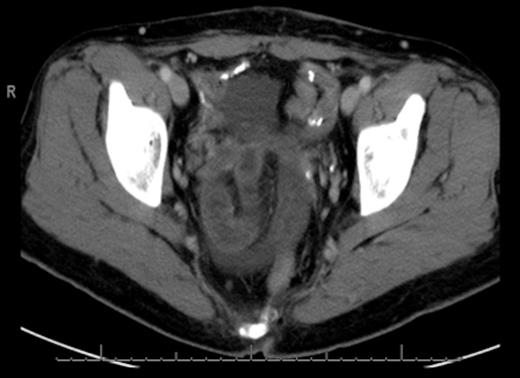

CT scan of the abdomen and pelvis revealed wall thickening and dilation of a few loops of small bowel located in the pelvis. We were not able to exclude closed loop obstruction (Fig. 1 & 2).